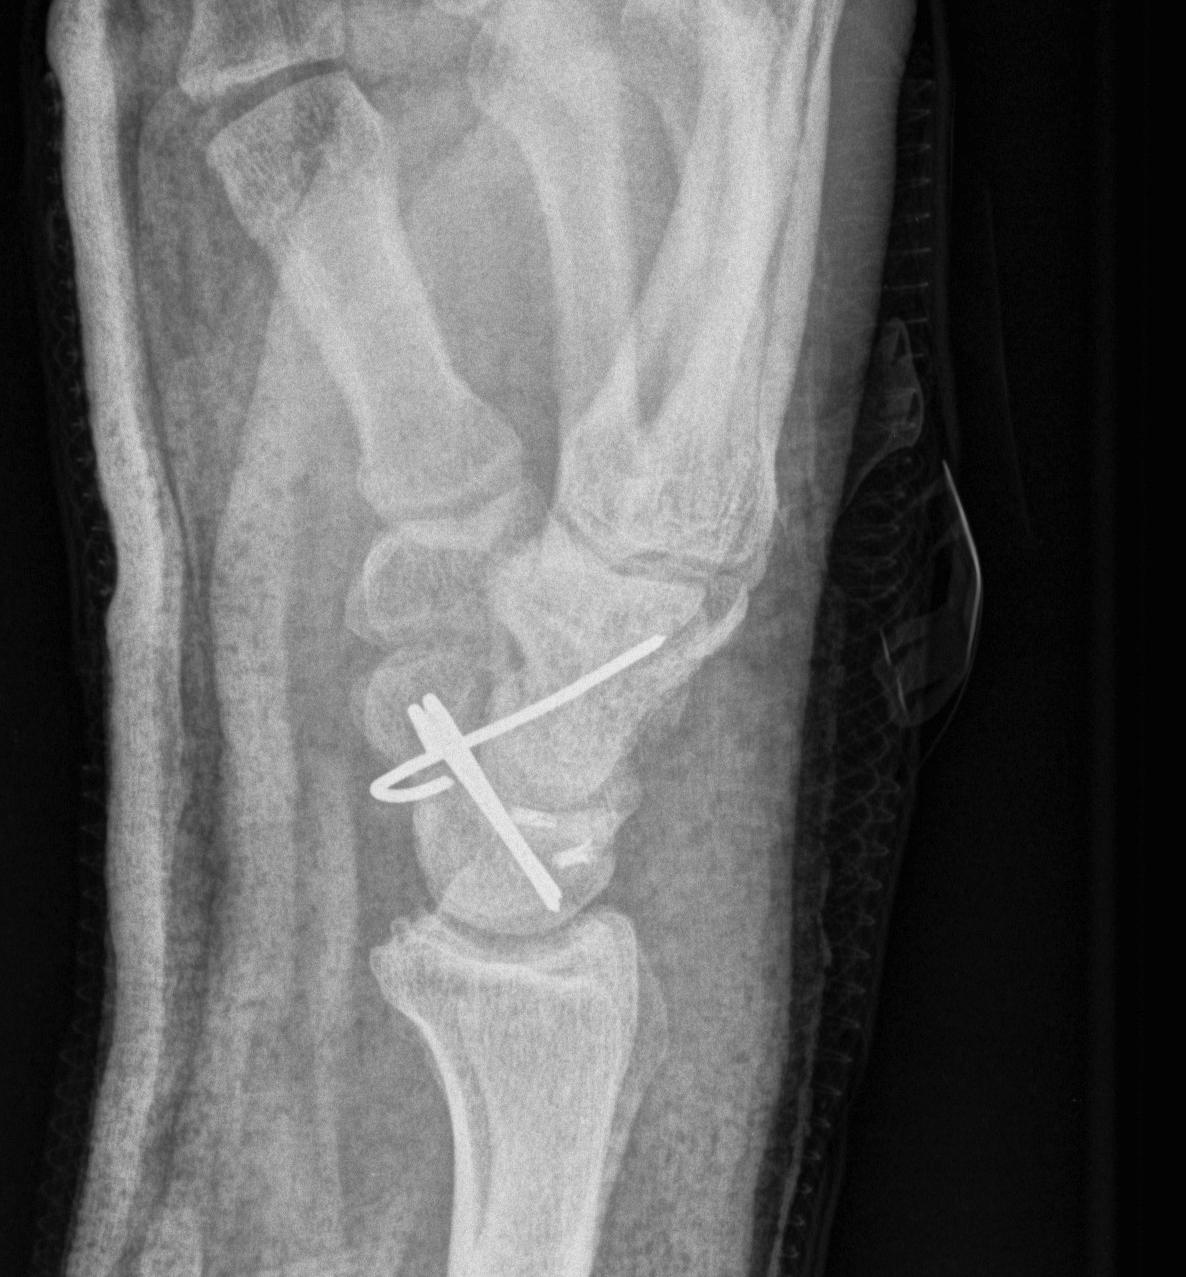

X-ray

Disruption of Gilula's 3 smooth carpal arcs

2. Lunate dislocates

- usually volar